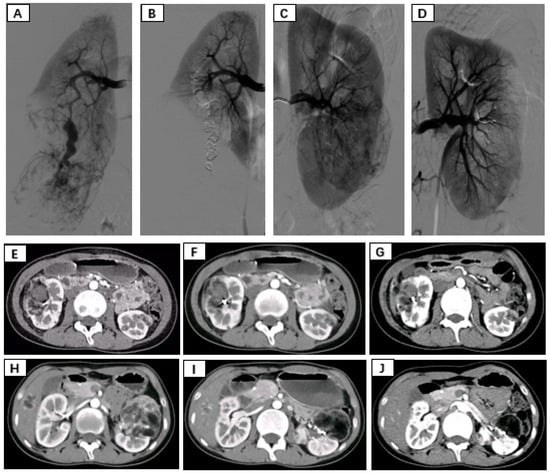

Patients were placed in the supine position and routinely disinfected and toweled. The right common femoral artery was used as the puncture point for all patients. Local anesthesia with 1% lidocaine was administered, and the modified Seldinger method was used for retrograde puncture of the right femoral artery. After successful puncture, a 6F sheath (Cordis, Hialeah, FL, USA) was inserted under the guidance of a 0.035 inch × 150 cm guidewire (Boston Scientific, Alpharetta, GA, USA), and a 5F PIG (Cordis, USA) catheter was advanced to the upper segment of the abdominal aorta. High-pressure injection angiography was performed to locate the opening of the renal artery and determine the number, morphology, and lesion location of the renal arteries, followed by selective renal arteriography. Under the guidance of a 0.035 inch × 150 cm supersmooth guidewire, a 5F C2 catheter (Cordis, USA) was advanced to the opening of the diseased side renal artery. Renal artery openings were localized using high-pressure syringe angiography to determine the number, morphology, and location of the renal arteries. Depending on the size of the target vessel diameter, microguidewires (Asahi Intecc Co., Ltd., Seto-shi, Japan) were used to guide the insertion of either a 1.98Fr or 2.6Fr coaxial microcatheter (Asahi Intecc Co., Ltd., Japan) into distal branches at levels two or three in the renal artery. High-pressure injection angiography again revealed signs such as direct bleeding from the extravasation contrast agent and tortuous enlargement with structural disorder along with vascular composition outlining tumor contours in blood supply arteries feeding into tumors. After careful assessment of the tumor’s blood supply, a suspension of polyvinyl alcohol (PVA) embolic agent (COOK, Bloomington, IN, USA) mixed with an appropriate amount of contrast agent (usually at a concentration of 30% to 40%) was prepared. Under vascular angiography and fluoroscopy, the PVA particle suspension was injected into the tumor-feeding artery through a microcatheter at an appropriate speed to avoid reflux. For patients with concomitant arterial aneurysms, embolization coils (COOK, USA) of suitable diameter and quantity were used for embolization based on the target vessel diameter. For patients without arterial aneurysms, if incomplete embolization was observed after the use of PVA particles, spring coils were used to embolize the main tumor-feeding artery. In cases where the tumor was supplied by multiple arteries, selective embolization of each branch vessel with appropriately sized PVA was performed to minimize damage to normal renal units. Subsequent DSA revealed no distal visualization or extravasation of contrast agent in the branch vessels supplying the renal tumors. The right femoral artery puncture site was closed using a vascular closure device followed by hemostatic compression and pressure bandaging. After completion of the procedure, the patient returned to the ward for bed rest with immobilization of the right lower limb for 24 h while being closely monitored for any signs of bleeding from the puncture site (Figure 1).

Figure 1.

(A,B) Immediate pre- and postembolization imaging of the right renal angiomyolipoma. (C,D) Immediate pre- and postembolization imaging of the left renal angiomyolipoma. (E–G) Rupture and hemorrhage of the right renal angiomyolipoma, followed by 3-month, 6-month, and 12-month follow-up contrast-enhanced CT showing a significant reduction in tumor size. (H–J) Pre-embolization, 3-month postembolization, and 6-month postembolization follow-up contrast-enhanced CT images of the left renal angiomyolipoma demonstrating a marked reduction in tumor size.

7. Follow-Up

The average follow-up period after surgery for both groups of patients was 22 months, and all patients received outpatient follow-up. In the SAE group, postembolization re-examination via bilateral renal CT revealed a significant reduction in tumor diameter, indicating remarkable therapeutic efficacy. During the follow-up period, neither group underwent further surgery, and there was no tumor recurrence. In the SAE group, the average tumor diameter decreased by 3.33 cm compared to that in the pre-embolization group (p < 0.05) (Table 4).